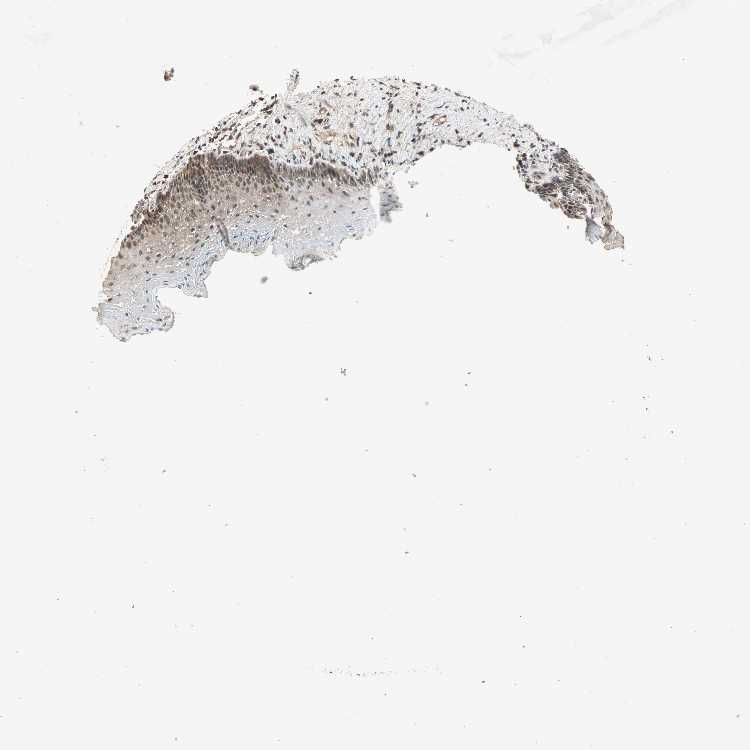

ESOPHAGUS - Antibody stainingi

Antibody staining in the annotated cell types in the current human tissue is reported as not detected, low, medium, or high, based on conventional immunohistochemistry profiling in selected tissues. This score is based on the combination of the staining intensity and fraction of stained cells.

Each image is clickable and will lead to virtual microscopy that enables deeper exploration of all samples and also displays staining intensity scores, fraction scores and subcellular localization as well as patient and tissue information for each sample.

Antibody HPA005651

Squamous epithelial cells High